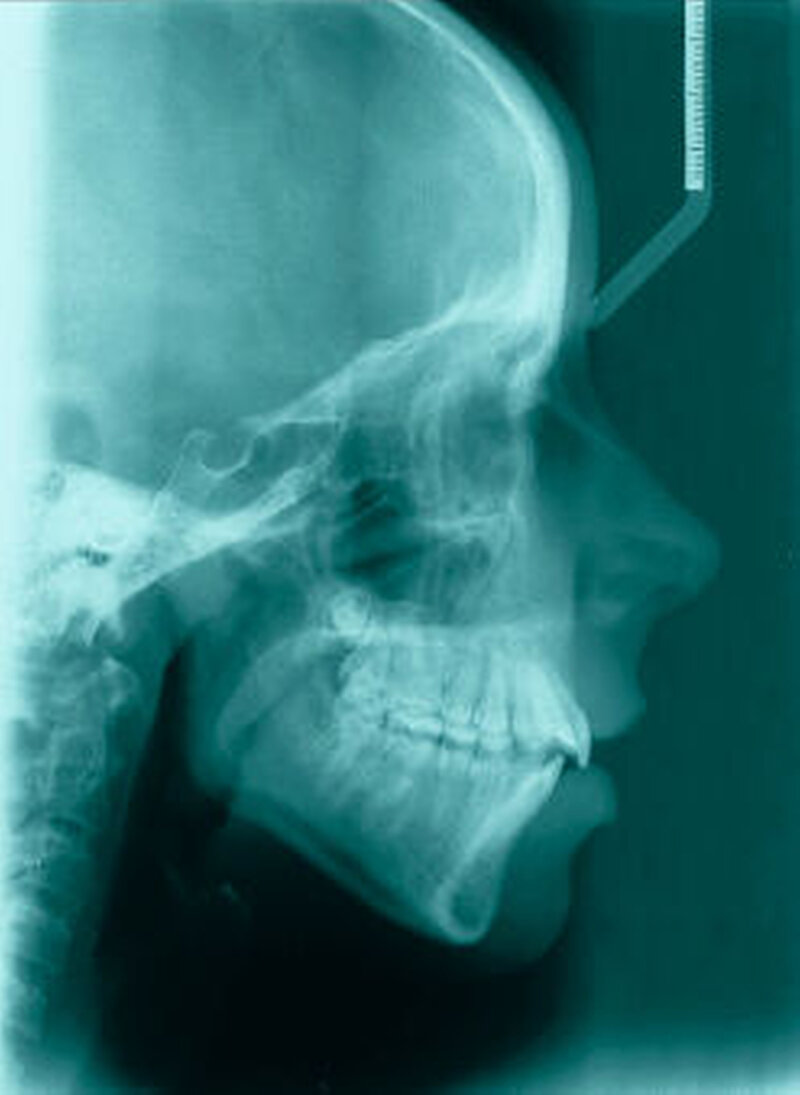

Die Fernröntgenseitenaufnahme in Abbildung 2a zeigt ein „rheumatisches“ Profil mit retraler, hypoplastischer Mandibula, oft kombiniert mit einer Schwäche des M. masseter auf der betroffenen Seite. Der Funktionsschmerz erzeugt „Kaufaulheit“. Die Gesichtsasymmetrie (Abbildung 2b) betrifft meist Kinn, aufsteigenden Ast und die Höhe der Kieferwinkel. Auch die nicht dentoalveoläre Mittellinienverschiebung kann auf eine JIA hinweisen. Kreuzbisse variieren in Abhängigkeit vom Grad der Unterkiefermittenabweichung. Gemeinsame Auftreten eines frontal offenen Bisses und eines vergrößerten Overjet sind als klinische Anzeichen zu bewerten.